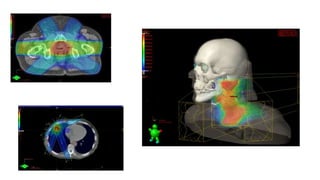

É a modalidade de radioterapia onde o planejamento é feito através de imagens digitais captadas por

um tomógrafo simulador e do mais moderno Sistema de Planejamento 3D.

Esta tecnologia tem permitido aos médicos radioterapeutas aumentar a dose de radiação no tumores,

e com isso melhorar os resultados dos tratamentos e reduzir a dose de radiação que atinge os tecidos

normais.

Como é possível aumentar a dose sem aumentar a toxidade?

Isto só é possível com o planejamento tridimensional, que é executado com o Multileaf (Colimadores

Multi-lâminas) que definem a dimensão e o formato exato da área irradiada (tratada).